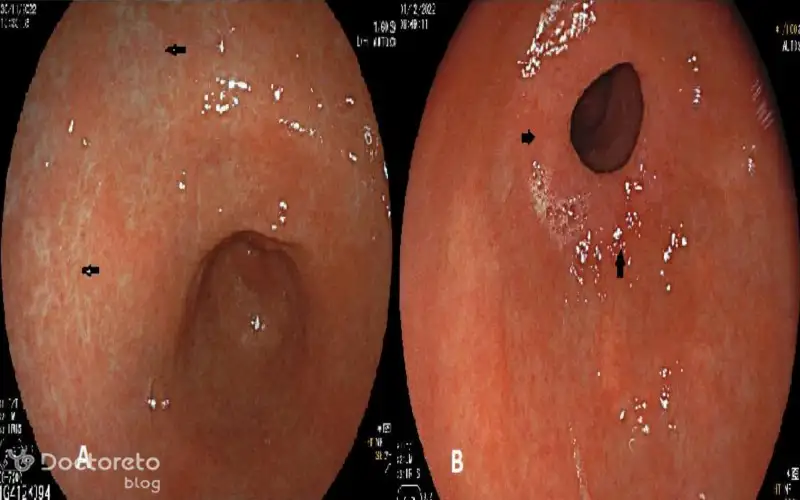

عکس آندوسکوپی سرطان معده بدخیم

آندوسکوپی یکی از روشهای مهم تشخیصی برای سرطان معده بدخیم است که در آن از یک لوله نازک با دوربین برای مشاهده داخل معده استفاده میشود. این روش امکان نمونهبرداری (بیوپسی) و مشاهده مستقیم تومور را فراهم میکند. این تکنیک در تشخیص زودرس بیماری نقشی مهم دارد.